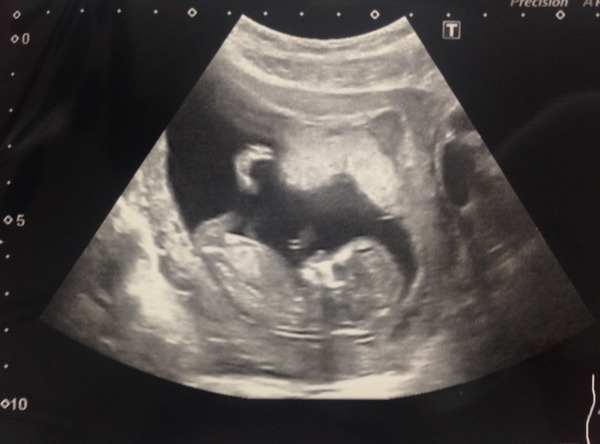

Great news on the scans, fab pics! Here's mine at 12+5 (over 2 weeks ago now!), no idea on any of the gender guessing theories but I'm convinced boy, any guesses?